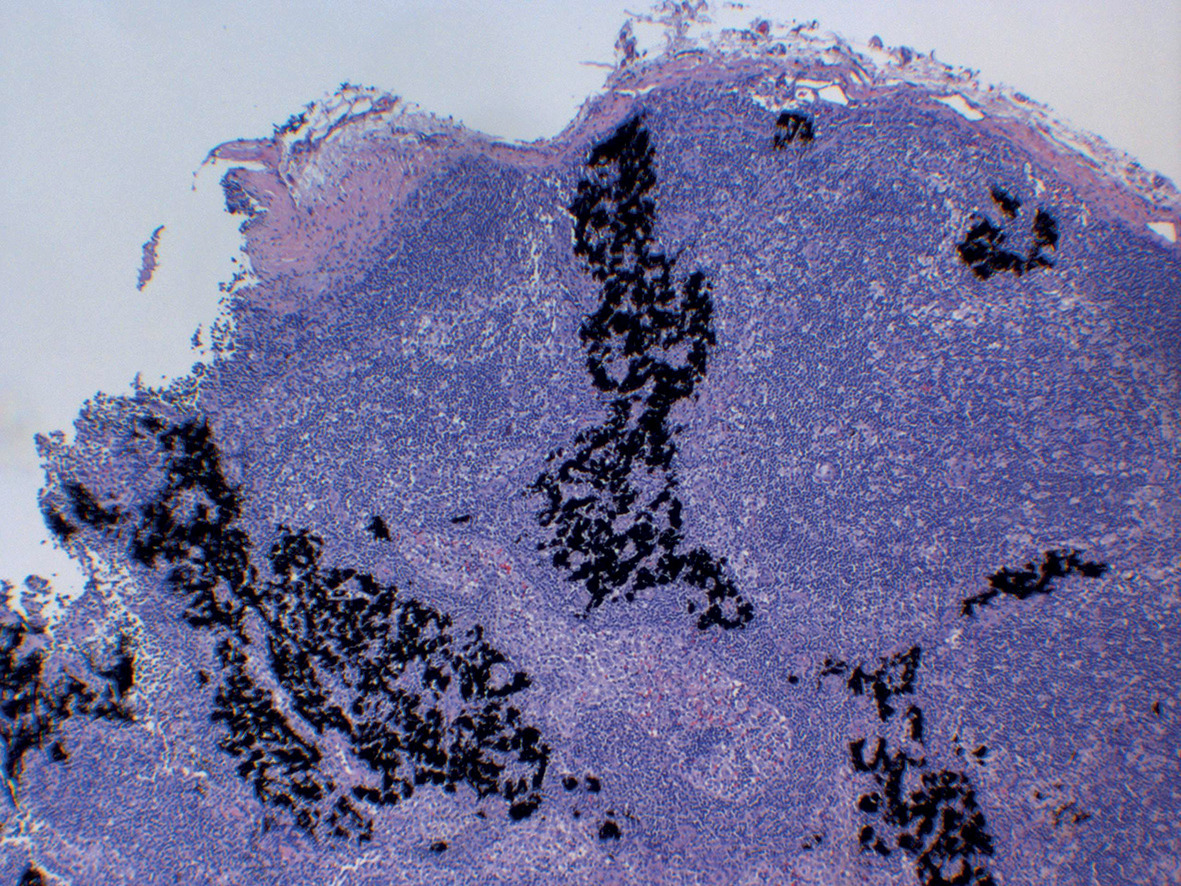

Sur le plan histologique, cette réaction peut être lichénoïde, eczématiforme, granulomateuse, sarcoïdosique (fig. 4) et pseudolymphomateuse. Le prélèvement est indispensable car un aspect granulomateux doit faire systématiquement rechercher une sarcoïdose systémique. S’il est lichénoïde, il faut éliminer de principe un lichen plan cutané ou muqueux. Les patch tests ne sont pas utiles en raison de résultats discordants. Ces manifestations persistent pendant des mois ou des années. Une résolution spontanée est possible mais dans un délai indéterminable.

Un grain de beauté ou une lésion déjà suspecte peuvent être « encrés » accidentellement. La migration des pigments dans les ganglions lymphatiques régionaux les colorent en noir faisant parfois poser à tort le diagnostic de métastase ganglionnaire de mélanome. Un tatouage doit toujours être mentionné en cas d’analyse de biopsie ou de curage ganglionnaire.